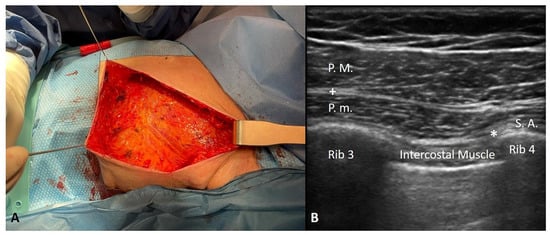

A 94-year-old woman with breast cancer and a positive sentinel lymph node biopsy was scheduled for a left radical mastectomy (Figure 1A). The patient’s medical history included pathologies such as dementia, hypertension, Mobitz I type BAV, hypothyroidism (the patient was receiving replacement therapy), osteoporosis, megaloblastic anaemia, recent interstitial pneumonia, and METS > 4 < 10. According to the classification of the American Society of Anesthesiologists (ASA), she was an ASA III, thus a patient with a severe systemic disease that was not life threatening.

The surgical team decided against using GA, orotracheal intubation, and intra or postoperative opioids because of the complications (delirium, disrupted psychomotor performance, cardio-respiratory depression, and ileus) linked to their use, and they hoped to discharge her as soon as possible after surgery in view of her age (94 years), clinical complexity, and comorbidities. The team opted for performing combined IPP and PSP blocks in the recovery room. This was carried out using an ultrasound linear probe (high frequency) and an ultrasound Sonosite Edge II machine in the following manner: a 50 mm Pajunk echogenic needle was used to inject ropivacaine 0.5% 10 mL (in the inter-fascial plane between the major and minor pectoralis muscles) +20 mL (in the inter-fascial plane between the pectoralis minor and serratus anterior muscles) (Figure 1B).

Figure 1. (A) A left radical mastectomy due to breast cancer and positive sentinel lymph node biopsy in an elderly female patient. (B) Combined interpectoral and pectoserratus plane blocks: a 50 mm Pajunk echogenic needle was used to inject ropivacaine 0.5% 10 mL (+: in the inter-fascial plane between the major and minor pectoralis muscles) + 20 mL (*: in the inter-fascial plane between the pectoralis minor and serratus anterior muscles).